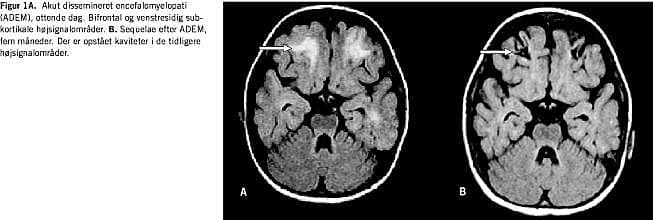

En MR-skanning af cerebrum (dag otte) viste akut disse-mineret encefalomyelitis (ADEM) (Figur 1A ).

En MR-skanning af cerebrum (fem måneder) viste ADEM-sequelae (Figur 1B ).